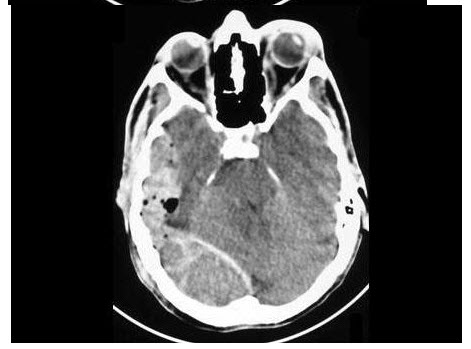

E.左侧冠状动脉瘤

110、多项选择题

女,64岁,反复尿频尿急尿痛6年余,尿常规检查:红细胞(++),白细胞(++)。CT扫描如图示,下列说法正确的是()

A.右侧输尿管下段管壁增厚,管腔狭窄

B.右肾积水

C.右侧输尿管上段扩张

D.考虑为慢性输尿管炎

E.考虑为输尿管移行细胞癌

111、多项选择题 椎缘骨的CT表现有哪些()